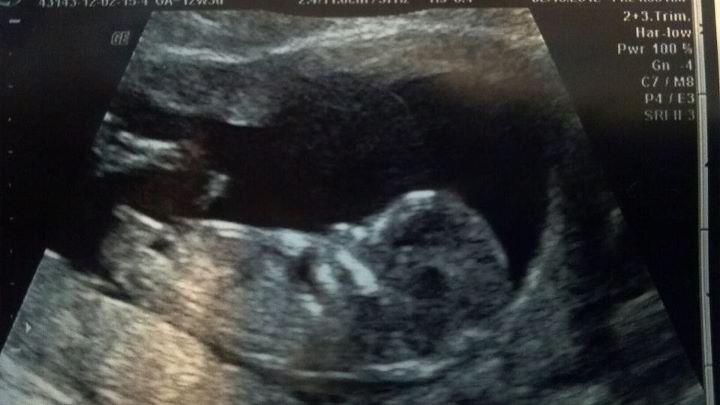

I think you're looking more like Adriana:DD:

Baby girly, good luck

baby girl !

Look like a girl.

Looks like a girl to me too. Good luck!

I think it's a little Adriana :) Good luck!